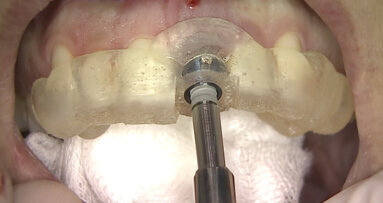

La tecnica chirurgica di distrazione ossea fa parte di quelle di chirurgia avanzata. Il dentista deve conoscere alla perfezione le tecniche di incisione dei lembi, quelle di osteotomia e di inserimento delle viti e placche d'osteosintesi. L’analgesia è solo locale. L'approccio si fa per via vestibolare realizzando una prima incisione al di sopra della linea mucogengivale. Lo scollamento del lembo è di tutto spessore. Il distrattore viene posizionato sulla zona ossea così esposta. L'osteotomia si fa fino alla corticale palatale. L'ausilio della piezochirurgia elimina il rischio di lesione della mucosa palatale o linguale. Il blocco osseo è mobilitato con uno scalpello e il distrattore fissato con viti di osteosintesi di 5 mm. La parte fissa è bloccata sulla base più apicale rispetto alla linea di osteotomia e la parte mobile del distrattore fissata sulla porzione da mobilizzare. Si procede alla verifica del buon posizionamento della DA attivandola un po' e riposizionandola come dapprima. L'intervento viene completato con suture senza nessuna trazione sui tessuti.

Il protocollo è codificato e deve essere rispettato come da sotto elencato:

- Giorno 1: posizionamento della DA.

- Giorno 8: Attivazione della DA (0.3 mm a giro).

- Giorno 16: fine dell'attivazione (variabile secondo la distanza desiderata).

- Giorno 45 (non prima): togliere la DA.

- Posizionamento dell'impianto lo stesso giorno o al 60° giorno.